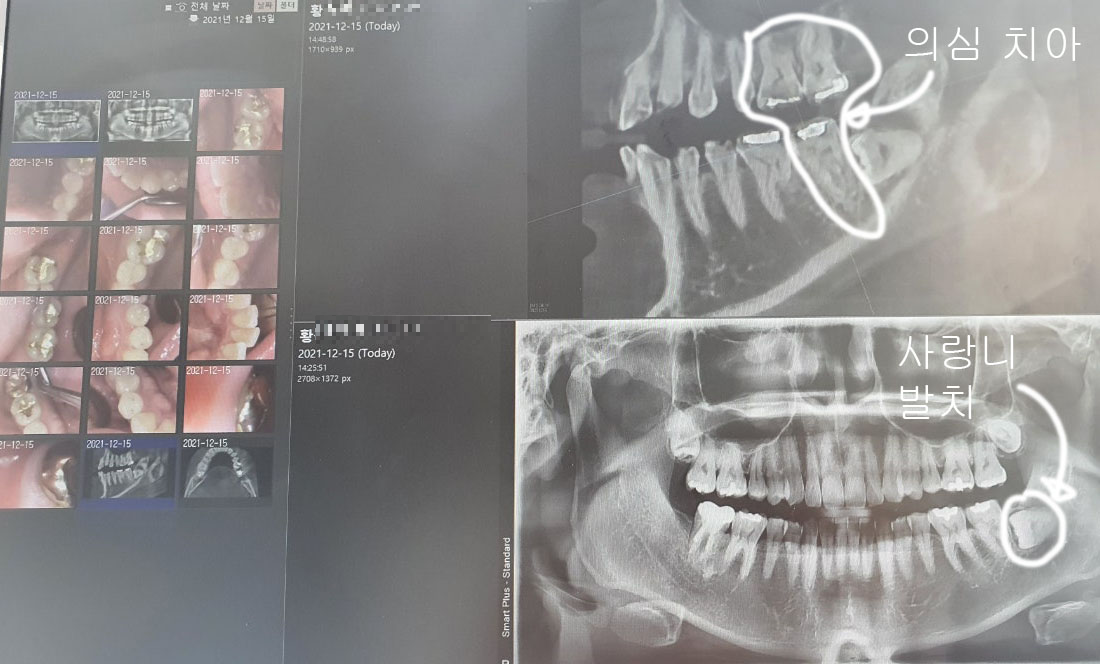

약 4년 전 왼쪽 아래 어금니 통증으로 1차 의심인 사랑니를 제거하면서 보니 왼쪽 아래 어금니 상태가 크렉이 있어서 당장을 쓸 수 있지만 시간이 지나면 위험할 수 있다고 안내받았고, 당시 치료는 완료했지만, 나중에 최악의 상황으로 임플란트까지 할 수 있을 가능성도 있다는 진단을 받은 적이 있었기에 이쪽이 의심이 가기도 했습니다.

이런저런 검사를 해보더니 통증치아가 어딘지 정확히 모르겠다며, 스케일링을 먼저 하고 의심되는 부분의 치료를 권유했습니다.

의심되는 왼쪽 아래 어금니, 왼쪽 위 어금니와 그 옆에 치아까지 총 3개의 치아를 모두 신경치로 + 레진 코어 + 지르코니아 치료를 권유하였습니다.